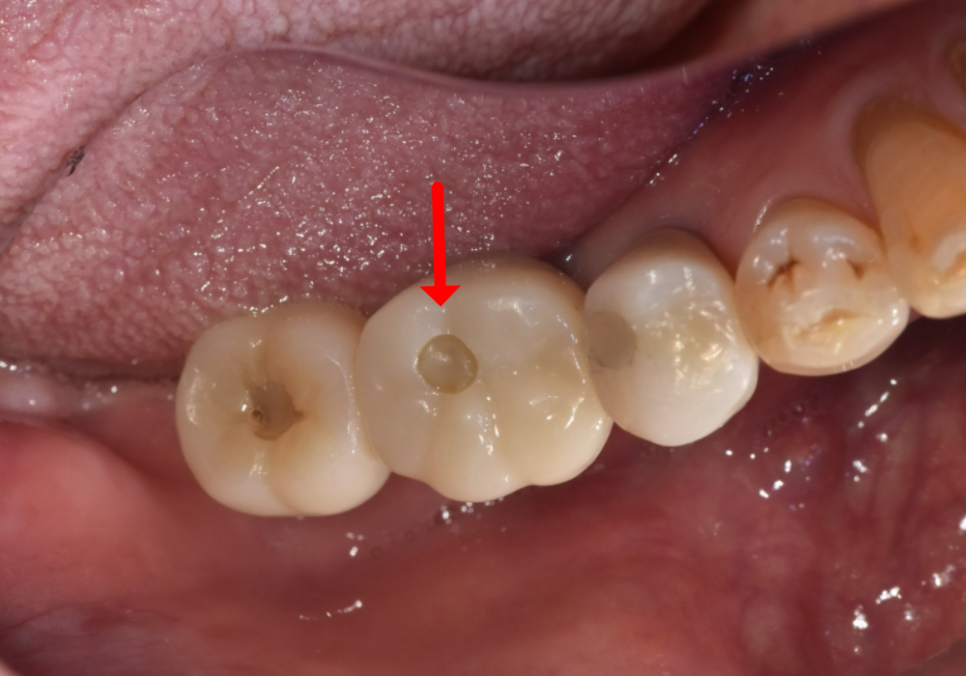

② SCRP 타입

(Screw Cement Retained Prosthesis)

접착제로 붙이긴 하지만,

씹는 면에 '비상구(나사 구멍)'

를 만들어두는 방식입니다.

평소에는 레진이라는

재료로 구멍을 메워두죠.

장점 : 유지 보수가 정말 쉽습니다. 메워둔 레진만 살짝 떼면 즉시 나사를 조일 수 있고, 잇몸 관리에도 훨씬 유리하죠.

단점 : 씹는 면에 작은 구멍이 보일 수 있지만, 어금니는 눈에 잘 띄지 않아 크게 문제 되지 않습니다.

이번에는 구멍이 없는 방식이 아니라,

씹는 면에 아주 작은 나사 구멍을 만들어는

'SCRP 방식'으로 변경했습니다.

240626